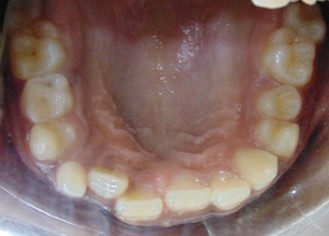

Before

After

Image 2